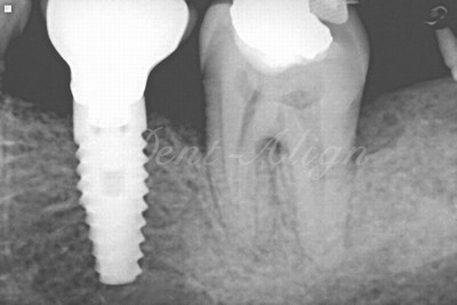

Diagnosis : The space present at the region of the missing tooth was inadequate to place a dental implant as the tooth present adjacent to the missing space had tipped into it.

a) Orthodontic phase : A micro screw orthodontic implant was used as a support to upright the tipped tooth.

b) Dental implant phase : After the space was created for the dental implant by orthodontics, dental implant with crown was placed.

Result : The missing tooth was replaced with an optimum sized implant and a good occlusion.